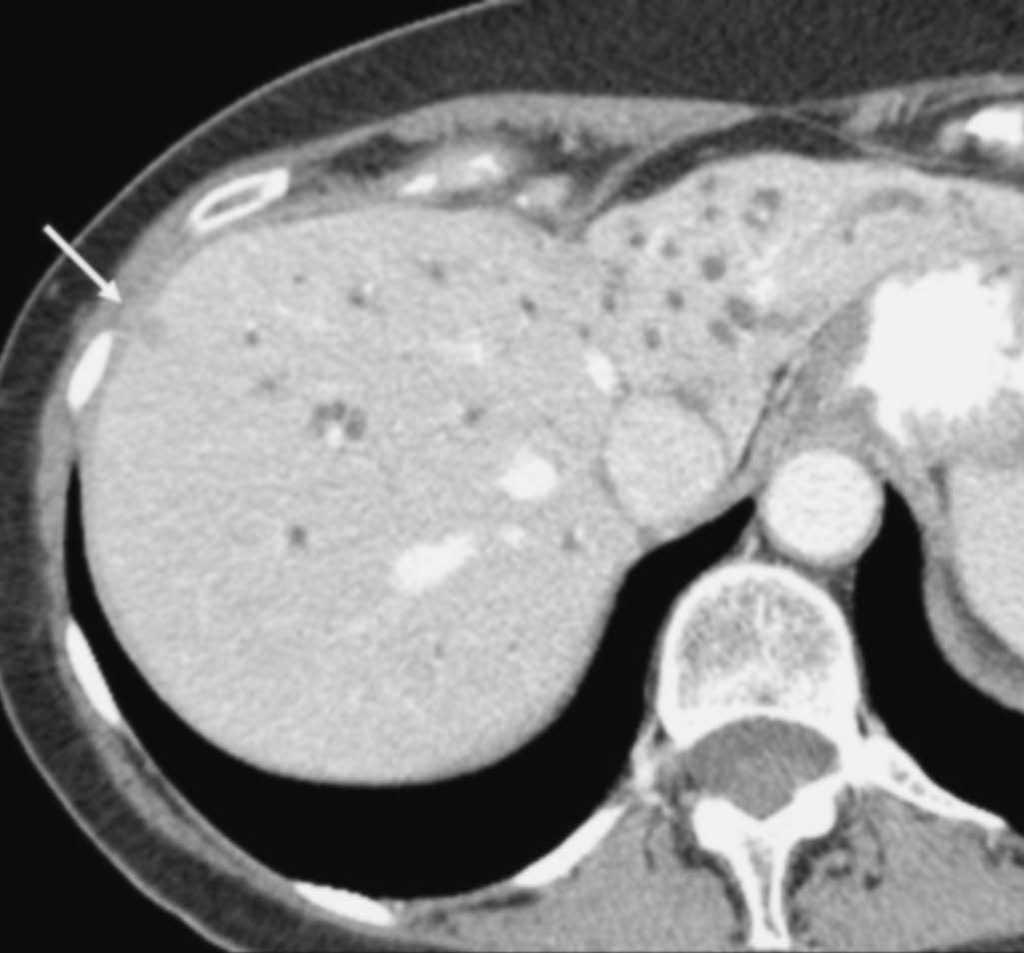

Metástasis hepáticas te;stasis hepáticas o peritoneales constituye un criterio definitivo de irresecabilidad tumoral, no obstante algunos estudios12,14,45 han sugerido la incapacidad de la TC para detectar lesiones metastásicas de pequeño tamaño (fig. 10). Vargas et al43, utilizando TCMC, presentan resultados similares, ya que de los 23 pacientes considerados resecables en base a los hallazgos de la TC, en 3 no se pudo llevar a cabo la resección. Dos de ellos presentaban metástasis hepáticas de pequeño tamaño y el paciente restante tenía pequeños implantes tumorales peritoneales. En nuestra experiencia32 la TC helicoidal bifásica tiene una baja sensibilidad para la detección de metástasis a distancia (55%), aunque con un alto valor predictivo negativo (90%) y una elevada precisión diagnóstica (88%).

Fig. 10.-. Estudio de tomografía computariazada en fase portal. Neoplasia de páncreas diseminada que dilata la vía biliar intrahepática. (A) Metástasis hepática subcapsular, infracentimétrica, hipodensa (flecha) en la fase venosa portal del estudio dinámico. (B) Se identifica una segunda metástasis (flecha) de menor tamaño, también subcapsular en el extremo hepático caudal.